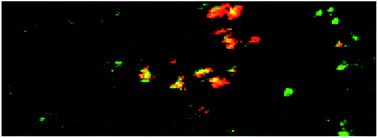

Silver nanoparticles (Ag-NP) are contained in many consumer products although their uptake especially by respiration bears potential risks for human health. Quantitative data about the systemic distribution of Ag-NP at the cellular level is strongly required to better understand the mode of action and to create meaningful in vitro models. In this paper we present a novel approach to identify cells in tissue sections by mass spectrometry imaging. Starting with a specific antibody bound to a cell marker protein we employed a double labelling strategy: a conventional secondary fluorescent antibody staining is followed by a labelling with a colloidal gold-coupled antibody directed against the same primary antibody. This allows identification of, e.g., regions of interest with conventional fluorescence microscopy and, thereafter, to detect identified cells by elemental mass spectrometry. The strategy circumvents the necessity to allocate mass-based signals to microscopic images. Unlike cost-intensive lanthanide-labelling the method is applicable to monoclonal and polyclonal primary antibodies. With this approach we confirmed the uptake of silver nanoparticles in alveolar macrophages and alveolar septal structures.